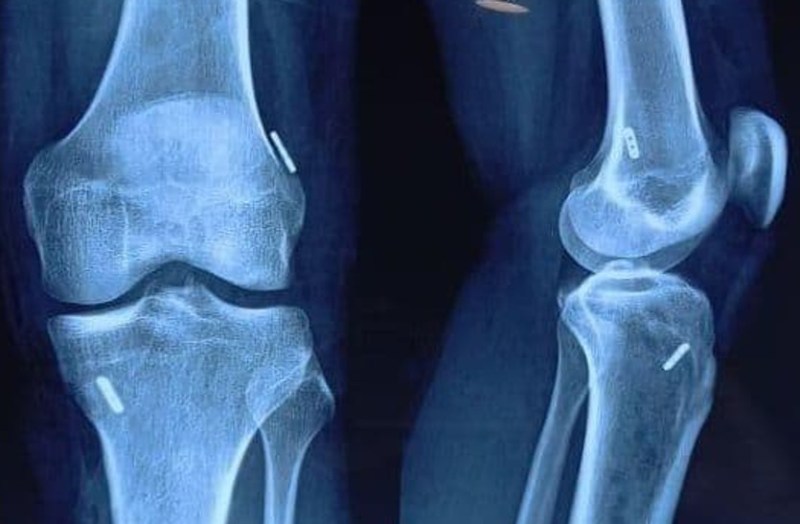

हाल ही दो खिलाड़ियों की लिगमेंट की स्पोर्ट्स इंजरी को इस विघि से ठीक किया गया है। सी.के.बिरला हॉस्पिटल के ऑर्थोपेडिक डॉ. आशीष के शर्मा ने 'ऑल इंसाइड आर्थ्रोस्कोपी एसीएल सर्जरी' की शुरुआत के साथ ही दो खिलाडिय़ों को इससे ठीक भी किया। 'ऑल इंसाइड आर्थ्रोस्कोपी एसीएल सर्जरी' लिगमेंट्स पुनर्निर्माण की एक नई शल्य क्रिया है जो खिलाडिय़ों को उन्हें चोट से पूर्व खेल स्तर में लौटाने में ज्यादा सफल पाई गई है।

डॉ. शर्मा ने बताया कि इस तकनीक में पारंपरिक विधि की बजाय लंबे बोन टनल नहीं बनाने पड़ते हैं और मात्र एक टेंडन ही यूज होता है, जिसकी वजह से दर्द भी नहीं के बराबर होता है। सिंगल टेंडन तकनीक होने की वजह से पैर की हैम्स्ट्रिंग मांसपेशी में पावर कम नहीं होती, जिससे खिलाडिय़ों को जम्पिंग में और रेस की शुरुआत में पुश-ऑफ या टेक-ऑफ में कमी महसूस नहीं होती। इस विधि में दर्द भी कम होता है, रीकवरी भी जल्दी होती है और स्पोट्र्स में वापसी भी बेहतर होती है। साथ ही भविष्य में यदि कोई रीविजन सर्जरी की आवश्यकता पड़े तो बोन स्टॉक बरकरार रहता है।